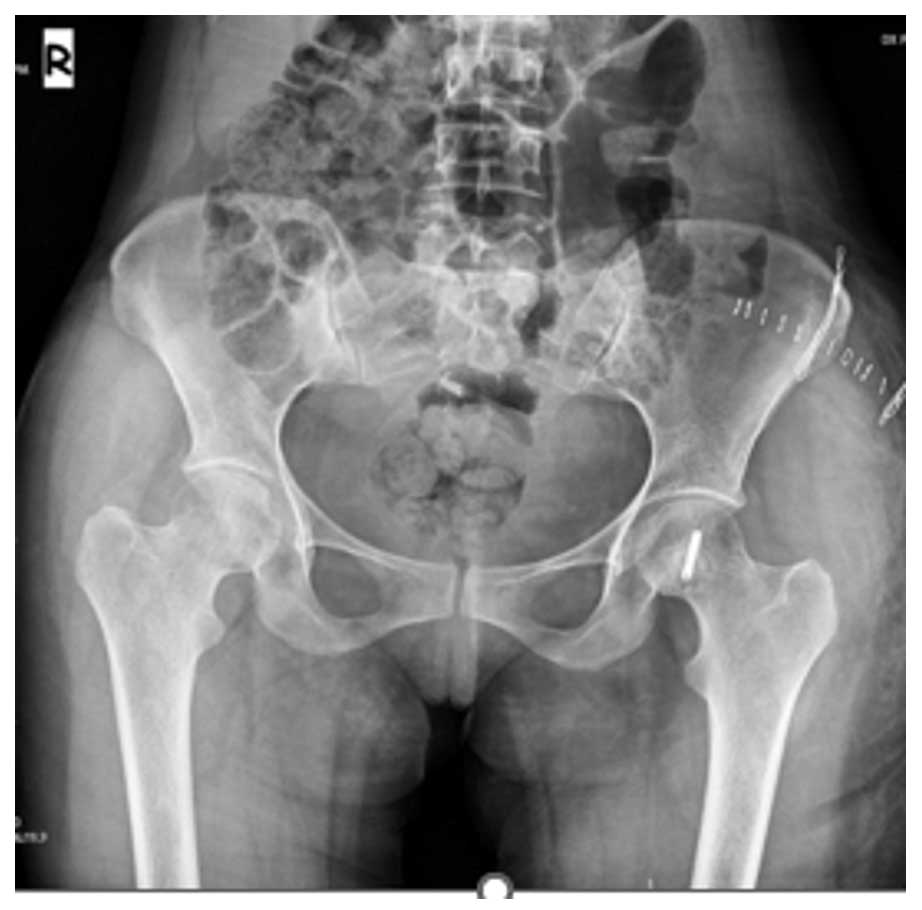

Ameliyat Öncesi: Röntgende düzensiz sınırlı , tomografide kortekste incelme ve kıkırdak doku içeriği, MR’da tümör sınırları görülmekte.